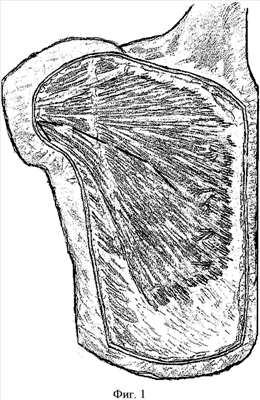

– отсекают абдоминальную часть большой грудной мышцы от места прикрепления к плечевой кости, расслаивают ее по ходу мышечных волокон (Фиг.1);